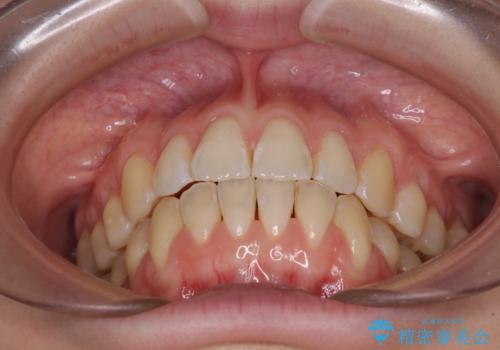

気になるデコボコとオープンバイト インビザラインでの矯正治療

- 前歯のデコボコと上下が開いていることを気にして来院された患者様です。

いわゆるオープンバイトは、インビザラインによる治療が適しているため、インビザラインにて治療を行うこととしました。

オープンバイトは容易に後戻りを起こすため、少しでも後戻りリスクを軽減するために舌癖改善のトレーニングをしっかりと行っていただきました。